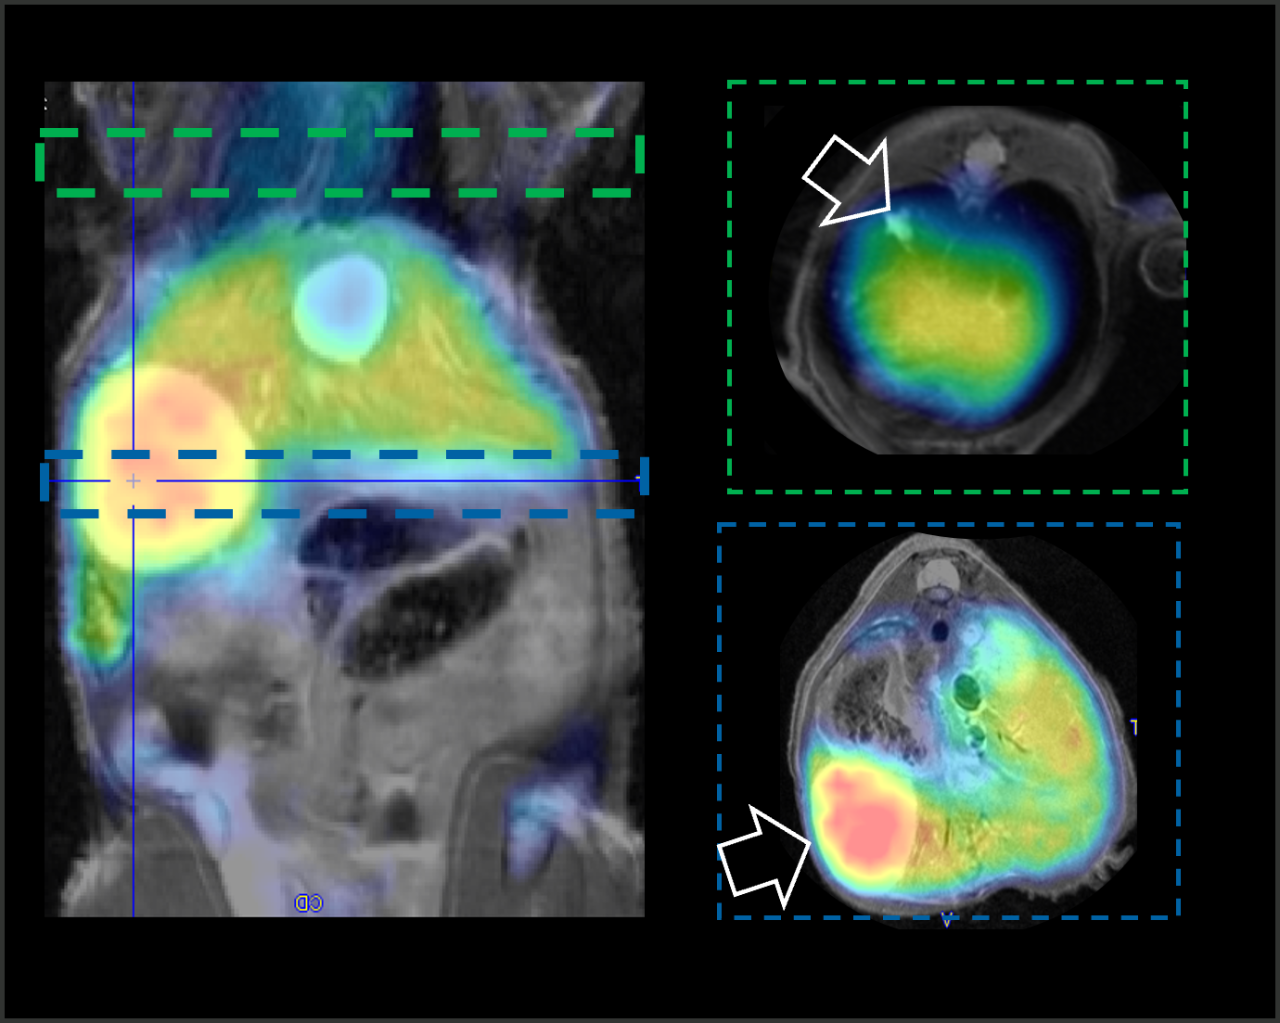

Combining PET with MRI enhances the capabilities to study detailed morphological changes in different organs and tumours, adding more precise information of the distribution and behaviour of the PET tracer.

Bruker’s sequential PET/MR instruments are offered at 3T for translational research and at 7T and 9.4T for high-field applications in mice and rats using Bruker’s BioSpec Maxwell MRI technology. This is combined with Bruker’s SiPM PET technology, providing the highest sensitivity, high spatial resolution and precise quantification across the entire FOV. A touch screen controlled motorized animal transport system simplifies the workflow and supports a broad spectrum of application fields, such as oncology, functional and anatomical neuroimaging, cardiac imaging and stroke models. All of this powered by the Paravision 360 software, allowing MRI users to follow familiar MR imaging workflows to obtain valuable PET/MR data immediately.